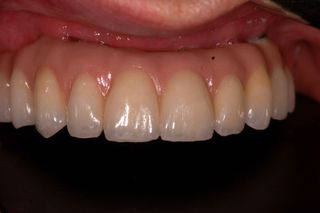

ALL-ON-7 CASE. UPPER, FULL ZIRCONIA BRIDGE.

45y.o male initially presented with failing upper dentition due to chronic advanced periodontitis (gum disease).

After thorough evaluation and diagnosis, which included Cone Beam CT scan, Digital Smile Design – DSD, 3D- intraoral Scanning etc, the treatment plan had been formulated.

All upper teeth had been extracted utilizing special surgical techniques for bone preservation and bone grafting. Among those were: Partial Extraction Therapy (PET), Bilateral Sinus Elevation (Sinus Lift).

Seven dental implants had been inserted using Digital Guided Placement Method. The surgical phase had been finalized with soft tissue grafting to insure proper gum seal around dental implants for long term success and to prevent peri-implantitis.

After completion of bone integration (healing) The final prosthetic phase had been accomplished with fabrication of the full contour zirconia non-removable (fixed) bridge.